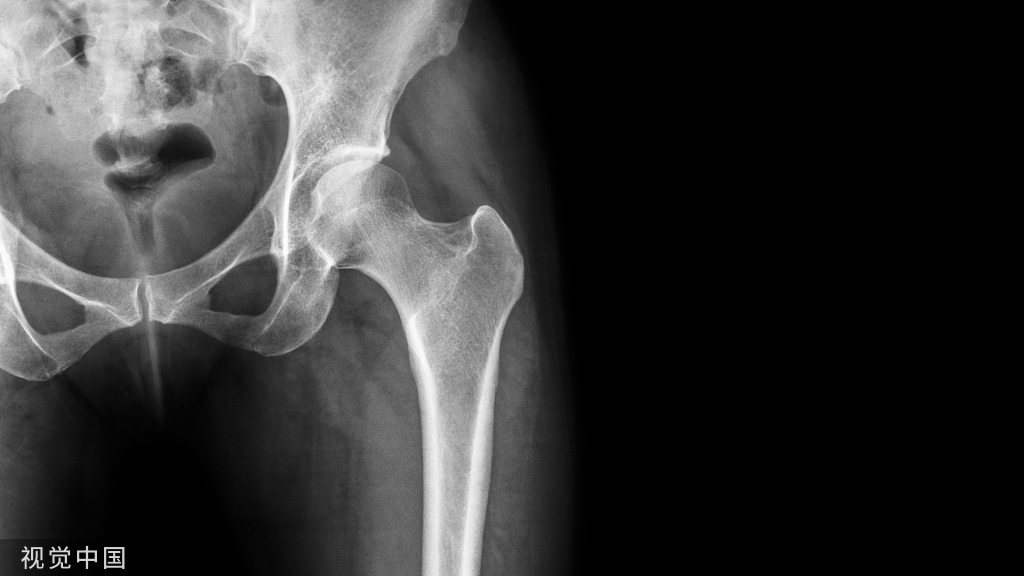

髋骨的X线解剖

常规投照正位(图1)。在X线像上,构成髋骨的三个部分融合于髋臼,可清晰分辨。髂骨翼的内侧1/4影像与骶骨影像重叠,外侧3/4因有髂窝而较透亮。髂嵴阴影较致密,边缘不光滑,外侧可见髂前上棘影,髂后上棘则重叠于骶骨影内。

弓状线及骨盆腔内侧壁形成复合影像,外侧可见弧形的髋臼阴影。髋臼阴影的上段粗而致密,中段较细,它向下绕过髋臼切迹前部的下缘,与耻骨体的内面形成一条“U”形的致密线,称为泪滴线(Koekler泪滴),泪滴线二脚之间的距离,即髋臼窝的厚度。

髋臼内下方的透亮影为闭孔。闭孔影的上界是耻骨上支、外侧界是坐骨体的下份,坐骨结节阴影与其重叠。坐骨棘的阴影呈三角形突向盆腔。

髋关节的X线解剖

常规拍摄正位(见图1)和侧位X线片。正位线片上,因髋臼三骨之间以“Y”形软骨相连,融合之前,表现为横行带状透亮影,其宽窄随着年龄变化而改变。年龄越小此透亮带越宽;年龄越大,透亮带变窄,15~17岁左右消失。股骨头大部套在髋臼内,表面光滑,为致密的细弧线。头的中心偏后下部有一小凹陷,是股骨头凹,有时可投影到股骨头弧线内侧,显示为小环形透亮圈。侧位片上,中央的凹窝是髋臼,呈半圆形的致密线。

图1 骨盆正位片